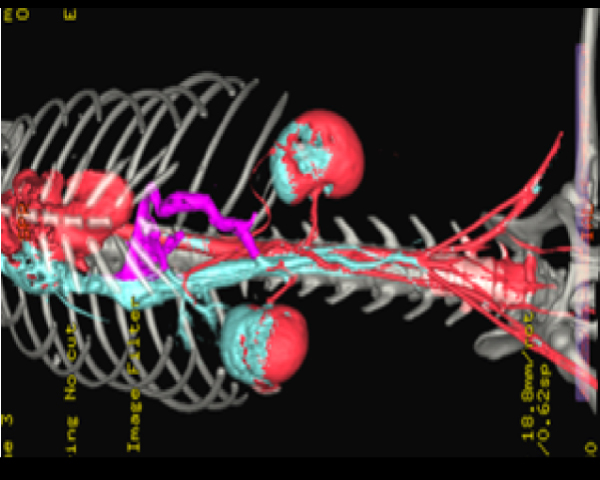

その後造影CT検査を行い、血管の評価を行います。

この症例の血管のCT画像